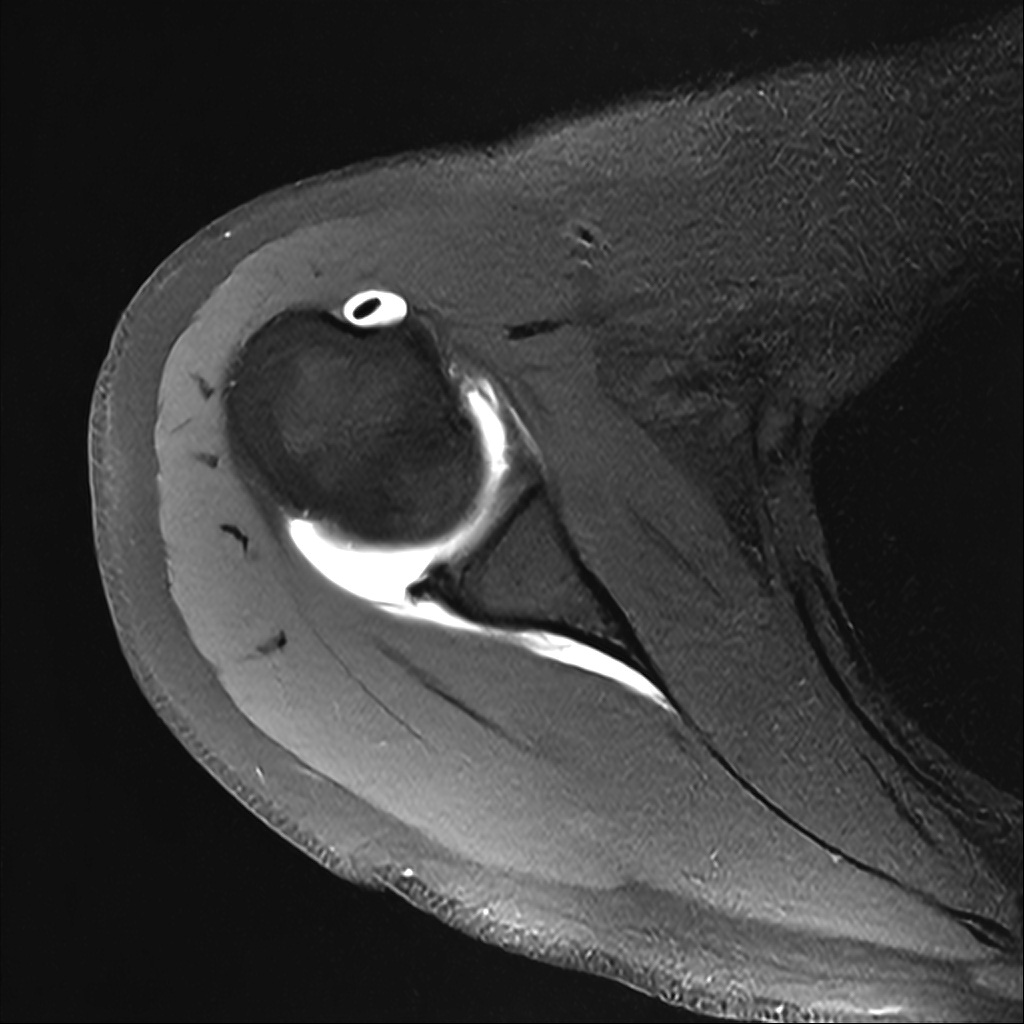

Mri 단면 영상으로 보아 어깨 관절 부위에서 이상 신호가 관찰되고 이는 관절 와순 파열의 가능성을 시사할 수 있습니다.

하지만 이영상만으로 정확한 진단은 불가능하고 정밀한 판단을 위해선 전체 시퀀스와 영상의학과 전문의의 공식판독이 필요합니다 특히 와순 파열은 위치와 동반 병변에 따라 해석이 달라집니다!